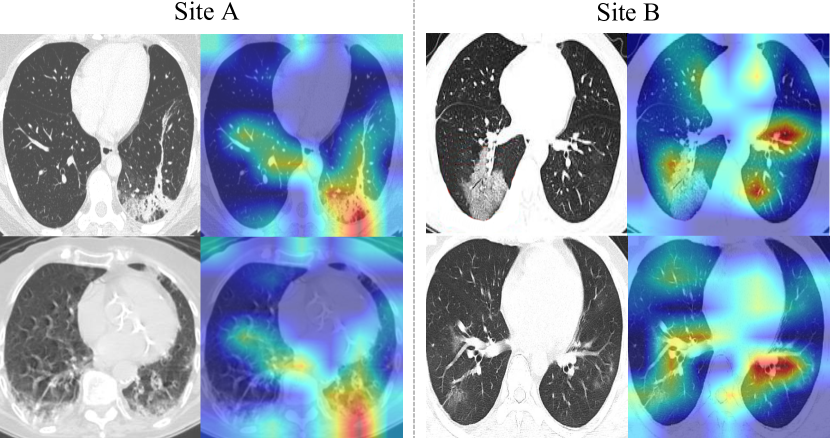

Refer to caption

Figure 1: The CT images of COVID-19 patients from two different clinical centers, showing data heterogeneity on the appearance and contrast.

A considerable amount of data-driven methods have been rapidly developed within this scenario, where the high accuracy is typically attributed to a collected large-scale training database [2, 3, 4], however, this is difficult to generally achieve in practice. Instead, to mitigate the insufficiency of single-site data amount, aggregating the CT imaging data from different hospitals is desired for establishing a cross-site learning scheme. For instance, Di et al. [5] proposed a hypergraph model with multi-site pneumonia data to achieve rapid identification of COVID-19 cases. Wang et al. [6] developed COVID-Net using data collected from different repositories to build an accurate deep learning classifier for X-Ray images. However, so far, a major limitation of these works is their negligence of the data heterogeneity across different clinical centers with various imaging conditions (e.g., scanner vendors, imaging protocols, etc). As illustrated in Fig. 1, the CT slices of COVID-19 patients from two different public datasets present apparently different image contrasts. This could potentially affect the model ability to extract robust and general representations as assumed. Previous studies on other medical imaging applications [7, 8, 9] have frequently observed that straight-forward joint learning with such heterogeneous datasets only brings limited improvement, or even sometimes underperforming individual models trained on a single dataset.

The CT images used in this study present notable appearance differences for COVID-19 patients across different severity. For examples as shown in Fig. 1, the mild patient may only contain a small lesion while severe patient can be infected almost in whole lung scope. Such large variance within the input space further presents difficulties for the model to explore a robust optimal solution from heterogeneous COVID-19 datasets. To address this problem, we expect a smooth learning process to facilitate the model optimization to reach a relatively robust solution. To this end, we propose to improve the COVID-Net learning strategy by adjusting learning rate more smoothly in a cosine annealing manner [31]. Specifically, denoting the total training epoch as T𝑇T, the learning rate at a current epoch t𝑡t is calculated as follows: